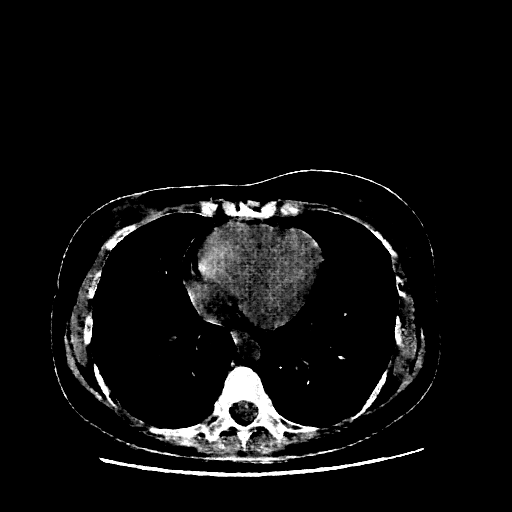

Image Grid

4Γ—3 grid: Rows show different image types (Original NATIVE, Reconstructed NATIVE, Original VENOUS, Generated VENOUS), Columns show windowing techniques (No Window, Lung Window, Mediastinum Window)

Generated VENOUS CT scan (A→B translation)

Mediastinum window (WL 40, WW 400 β†’ Low βˆ’160, High +240)